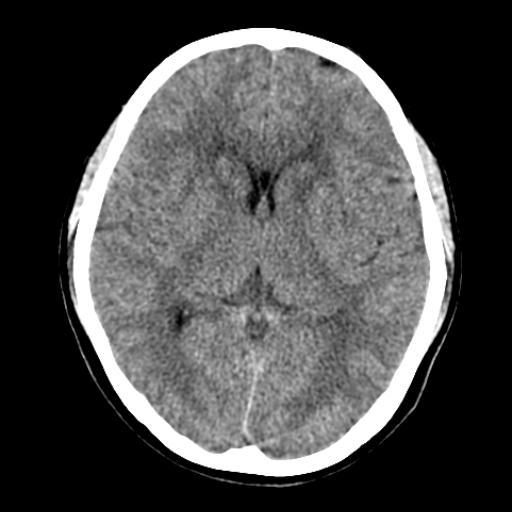

40f头晕十多天,右上肢麻木一天

脑白质变性或ms

脑白质脱髓鞘改变。

脑白质病;建议行mri检查。